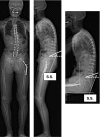

Introduction: The role of the pelvic area in sagittal balance is evident for spinal surgeons, but the influence of the coxofemoral joint is underestimated and inadequately explained by conventional imagery. Comprehensive analysis of the pelvic and subpelvic sectors as part of the sagittal, frontal and cross-sectional balance of the trunk sheds new light on some spinal diseases and their relation to the pelvis.

Methods: This analysis, based on innovative radiologic methods as the EOS(®) technology but also on a new look at conventional imaging makes it possible to better analyze standing lateral images and seated images.

Results: Disturbances can come from atypical morphotypes or from unusual postures as in aging spine. The measurement of available extension and the concept of available flexion provide new information regarding individual's adaptation to the imbalance induced by disorders of the spine or lower limbs.